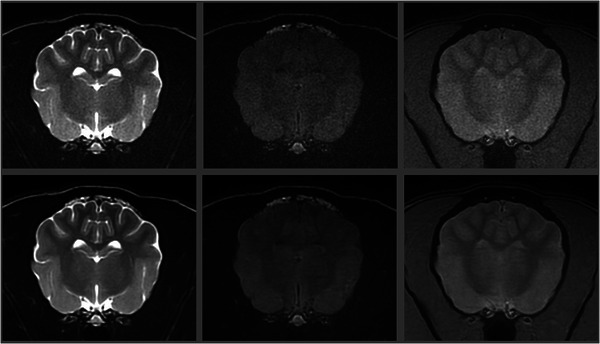

In this analytical cross-sectional method comparison study, we evaluated brain MR images in 30 dogs and cats with and without using a DICOM-based deep-learning (DL) denoising algorithm developed specifically for veterinary patients. Quantitative comparison was performed by measuring signal-to-noise (SNR) and contrast-to-noise ratios (CNR) on the same T2-weighted (T2W), T2-FLAIR, and Gradient Echo (GRE) MR brain images in each patient (native images and after denoising) in identical regions of interest. Qualitative comparisons were then conducted: three experienced veterinary radiologists independently evaluated each patient's T2W, T2-FLAIR, and GRE image series. Native and denoised images were evaluated separately, with observers blinded to the type of images they were assessing. For each image type (native and denoised) and pulse sequence type image, they assigned a subjective grade of coarseness, contrast, and overall quality. For all image series tested (T2W, T2-FLAIR, and GRE), the SNRs of cortical gray matter, subcortical white matter, deep gray matter, and internal capsule were statistically significantly higher on images treated with DL denoising algorithm than native images. Similarly, for all image series types tested, the CNRs between cortical gray and white matter and between deep gray matter and internal capsule were significantly higher on DL algorithm-treated images than native images. The qualitative analysis confirmed these results, with generally better coarseness, contrast, and overall quality scores for the images treated with the DL denoising algorithm. In this study, this DICOM-based DL denoising algorithm reduced noise in 1.5T MRI canine and feline brain images, and radiologists' perceived image quality improved.

Abstract Image